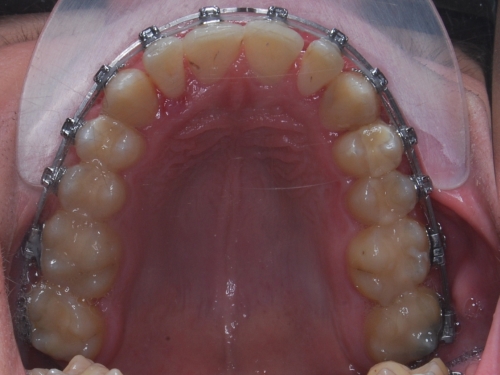

V naší ordinaci používáme kvalitní samoligovací zámky v kovovém provedení. U moderních, samoligovacích zámků dochází k nižšímu tření mezi zámkem a drátem než u zámků s gumičkami, což zjednodušuje léčbu a může jí zrychlit až o 30%. Malé tření zámků, spolu s dalšími prvky, umožňuje ve většině případů vyrovnání zubů bez nutnosti extrahovat některézuby. Používáme pouze variantu v kovovém provedení. Bílé keramické zámky již nepoužíváme z důvodu poměrně vysokého příplatku, který se v součtu blíží ceně rovnátek foliových, která jsou výrazně estetičtější a pohodlnější. Výhody samoligovacích zámků oproti klasickým zámkům s gumičkami:

Samotné použití samoligovacích zámků neznamená lepší léčbu než při použití zámků a gumičkami.

Je třeba, aby byl lékař vyškolen na tento systém, což je specifický přístup k rovnání zubů. V České republice se touto pokrokovou metodou rovnání zubů zatím zabývá jen menší část lékařů.